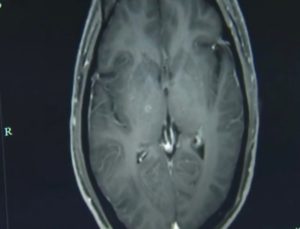

Se você é fã de carne de porco, o caso do chinês Zhu Zhongfa talvez torne você ainda mais exigente quando o assunto é o bom preparo desse alimento. Isso porque mais de 700 ovos de tênia foram encontrados no cérebro do homem, após ele ingerir um caldo com carne mal cozida.

Segundo os médicos de Zhu, o paciente de 46 anos foi parar no Hospital da Universidade de Zhejiang, no leste da China, apresentando graves convulsões, que se assemelhavam a um quadro de epilepsia. Ele já havia sido hospitalizado antes, com tontura e forte dor de cabeça, mas recusara qualquer tipo de tratamento por não querer gastar dinheiro.

Vale lembrar que a infecção também pode ocorrer em outras partes do corpo. Isso porque, após ingeridos, os ovos do verme eclodem por conta do fluido digestivo intestinal e permitem que a larva perfure as paredes do intestino, entrando na corrente sanguínea e chegando a diferentes partes do corpo.

Como o cérebro humano é muito vascularizado, os animais costumam se instalar por lá. Ainda assim, outras regiões também estão em risco: o próprio Zhu apresentou infestação nos pulmões.